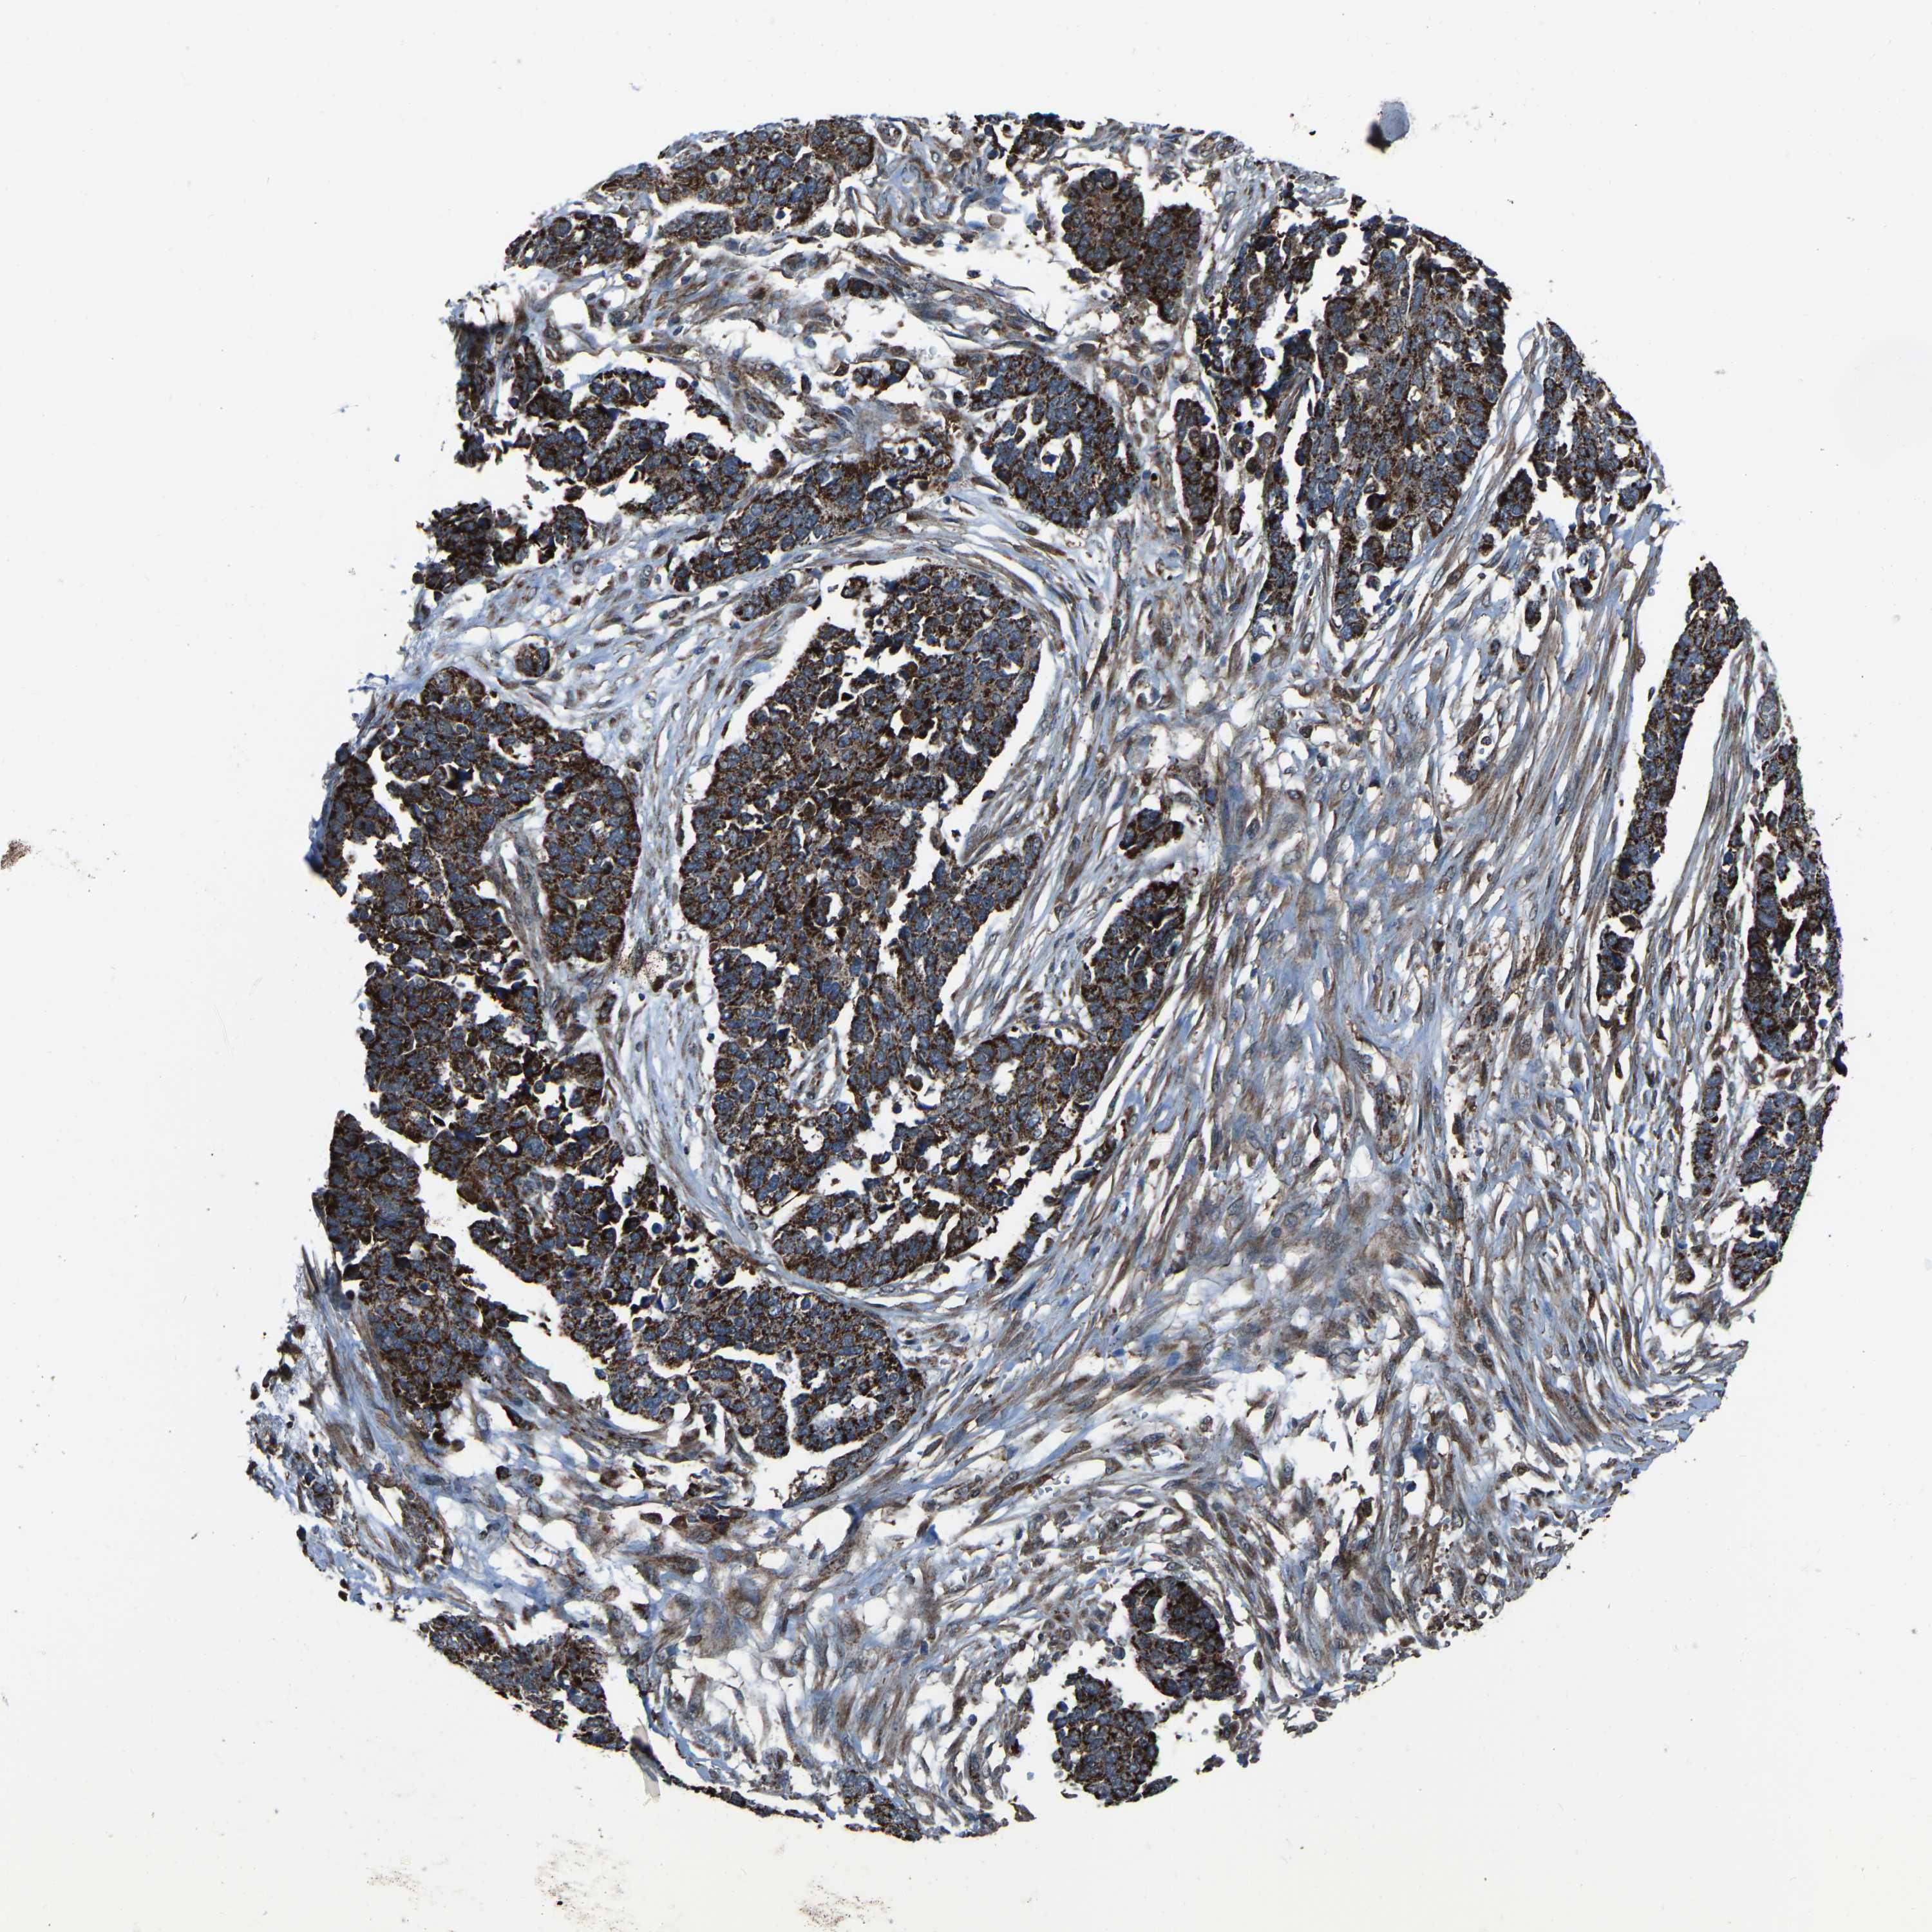

OVARIAN CANCER - Protein expressioni

A mouse-over function shows sample information and annotation data. Click on an image to view it in a full screen mode. Samples can be filtered based on level of antibody staining by selecting one or several of the following categories: high, medium, low and not detected. The assay and annotation is described here.

Note that samples used for immunohistochemistry by the Human Protein Atlas do not correspond to samples in the TCGA dataset.

Antibody stainingi

Antibody staining in the annotated cell types in the current human tissue is reported as not detected, low, medium, or high, based on conventional immunohistochemistry profiling in selected tissues. This score is based on the combination of the staining intensity and fraction of stained cells.

Each image is clickable and will lead to virtual microscopy that enables deeper exploration of all samples and also displays staining intensity scores, fraction scores and subcellular localization as well as patient and tissue information for each sample.

Antibody HPA017919

Antibody CAB006246

High

Medium

Low

Not detected

Cystadenocarcinoma, serous, NOS